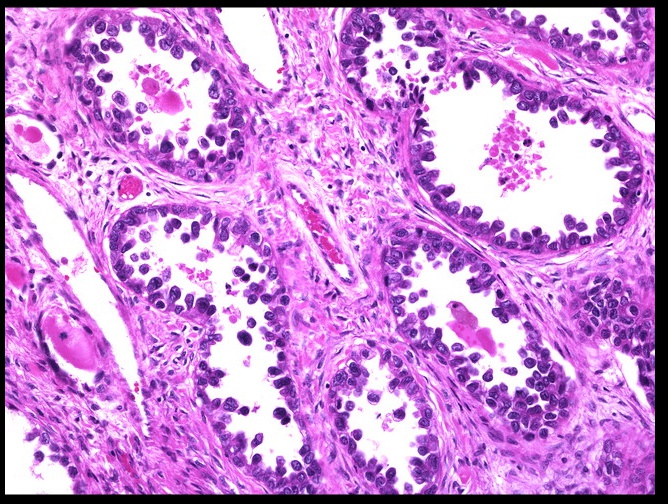

Clear cell adnocarcinoma:

Hobnail nuclei:

_Clear Cell Adenocarcinoma of the vagina is a rare, malignant tumor of glands with clear cytoplasm that is a complication associated with diethylstilbestrol-associated vaginal adenosis. It is commonly associated with exposure to DES in utero (Estrogen crosses placenta, distrupting development of squamous epithelium)

_When viewed microscopically, the tissue demonstrates cells with hyperchromatic nuclei (also known as "Hobnail" nuclei) protruding into the gland lumen.